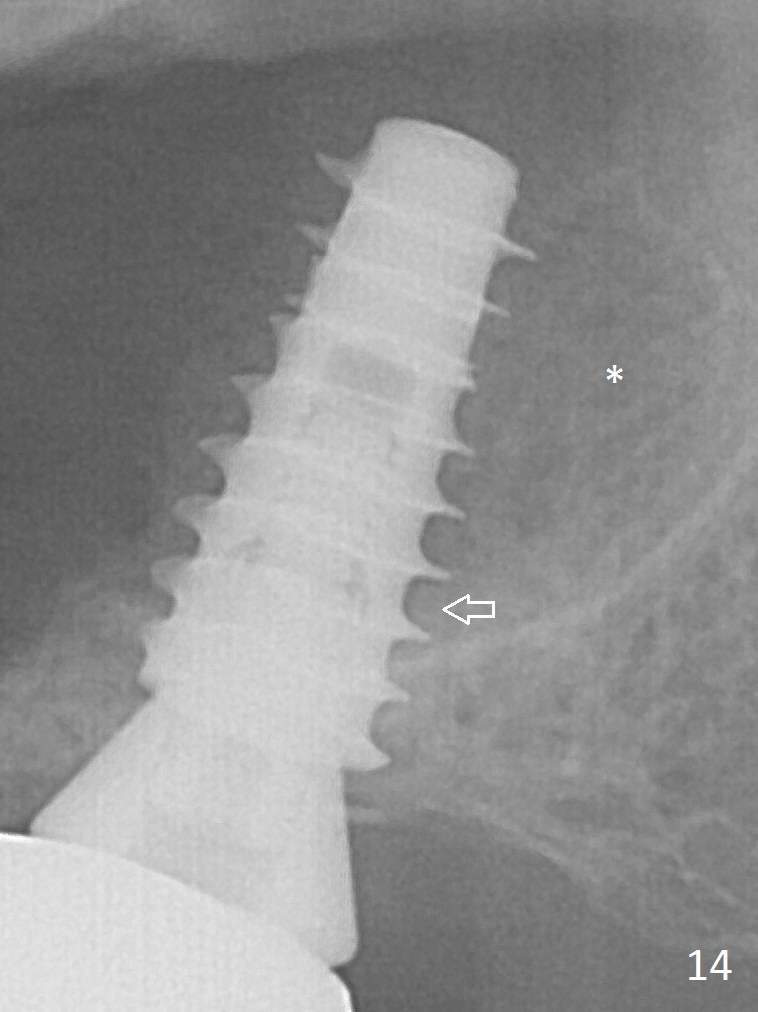

After placing allograft for sinus lift (Fig.6 >), a 5x11 mm IBS implant is placed with insertion torque ~ 50 Ncm. A 6x4(3) mm pair abutment is placed, followed by bone graft in the remaining sockets (*).